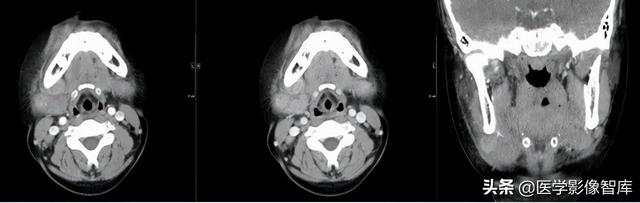

翼颌间隙、咽旁间隙

左下阻生齿拔除术后10天,伴吞咽疼痛4天。

手术导致的翼颌间隙及咽旁间隙脓肿形成。